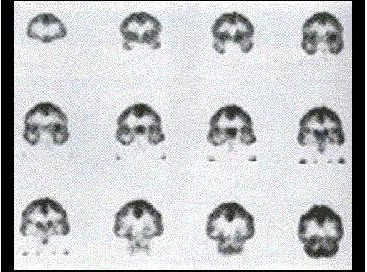

男,32岁,确诊左颞叶胶质母细胞瘤Ⅳ级,手术切除病灶,术后放疗2个月,化疗3个疗程;现距放疗结束17个月。查体:右上肢轻度乏力,骶尾部及双足麻木,排便困难;检查:MRI示左颞叶肿瘤局部复发可能。行PET/CT显像全身检查如图。最可能的诊断()。

A.左侧颞叶术后瘢痕组织改变

B.左侧颞叶肿瘤复发

C.恶性肿瘤沿椎管种植性转移

D.马尾种植性转移灶

E.以上都不是